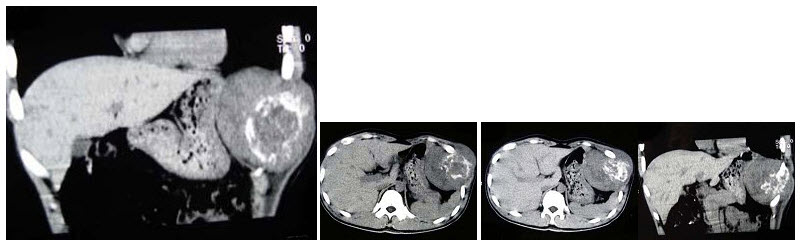

11、单项选择题

男,50岁,患乙肝多年,现腹胀,右上腹痛,消化不良,消瘦、乏力、贫血、黄疸,血清转氨酶升高,白蛋白/球蛋白比值倒置。CT检查如下图,最可能的诊断是()

A.肝硬化、肝癌

B.肝硬化、腹膜后淋巴结肿大

C.肝硬化、肝癌、腹膜后淋巴结肿大

D.肝硬化、门脉高压、脾大

E.肝硬化、脾大

12、单项选择题

男,65岁,腋下触及肿大包块,全身浅表淋巴结肿大,结合所示图像,最可能的诊断是()

A.双侧肾上腺腺瘤

B.双侧肾上腺增生

C.双侧肾上腺淋巴瘤

D.双侧肾上腺转移癌

E.肾上腺癌